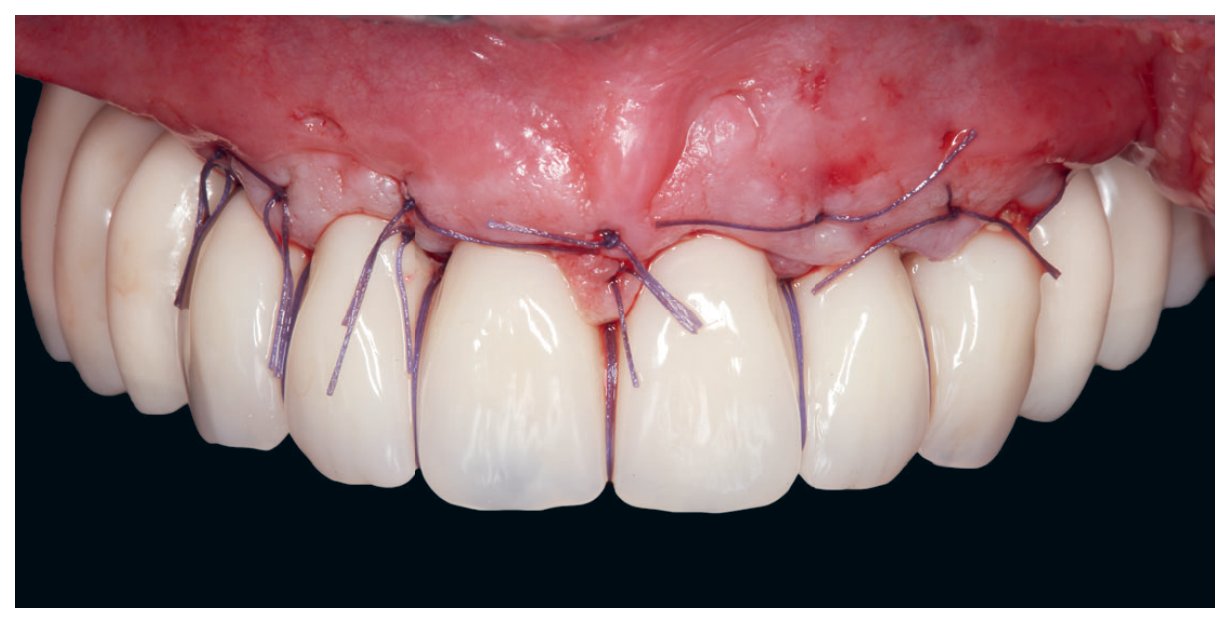

Photos cliniques illustrant des situations d'édentement complet et de passage à l'édentement

Validation du montage et élimination de la crête flottante

• le point interincisif est situé verticalement trop bas : cette possibilité est fréquemment associée à un sourire gingival. Il convient alors de remonter le point interincisif et de le situer par rapport au point interincisif actuel, en tenant compte de la quantité de tissus à réséquer pour masquer la transition fausse gencive et « gencive » naturelle lors du sourire. Si la perte osseuse entourant les dents fait anticiper la présence de fausse gencive dans la future restauration, il est conseillé de masquer cette jonction entre la prothèse et les tissus naturels pour se prémunir de tout défaut pouvant remettre en cause l'esthétique antérieure ;

• dans le cas d'une résorption faible, reconstruction de type FP1 : prothèse conjointe conventionnelle sans fausse gencive. Dans cette indication, la plus grande précision est nécessaire aux émergences implantaires, qui doivent toutes être strictement dentaires en évitant les espaces interproximaux, sous peine de compromettre fortement le résultat esthétique final. Une émergence strictement cingulaire pour les dents antérieures est nécessaire de façon à préserver un maximum de soutien pour le matériau cosmétique et ainsi éviter sa fragilisation. Dans ces cas de faible résorption, la visualisation de l'espace occlusoprothétique disponible permet également de confirmer une indication éventuelle d'ostéotomie verticale en cas de sourire gingival trop prononcé ou en cas d'un défaut éventuel d'orientation du plan d'occlusion, qui doit être strictement parallèle aux lignes bipupillaire et bicommissurale ;

• dans le cas d'une résorption moyenne, reconstruction de type FP2 : la prothèse peut présenter des émergences radiculaires ou un tout petit peu de fausse gencive, mais se rapproche aussi d'une prothèse conjointe conventionnelle ; dans cette indication, le positionnement implantaire nécessite une précision aussi stricte que dans l'indication précédente. Dans ces cas de résorption moyenne, la visualisation de l'espace occlusoprothétique disponible permet également de confirmer une indication éventuelle d'ostéotomie verticale de façon à masquer la future ligne transition entre la prothèse et la gencive naturelle, ou bien à nouveau pour corriger un défaut d'orientation du plan d'occlusion. Il faut également prêter attention dans cette indication aux cas présentant un décalage horizontal trop prononcé qui pourrait donner une impression de vestibuloversion prononcée des dents prothétiques : dans ces cas, une ostéotomie verticale peut être indiquée pour améliorer le profil d'émergence du bloc incisive-canin par rapport à la crête osseuse. On bascule alors dans ce cas dans une prothèse de type FP3 ;